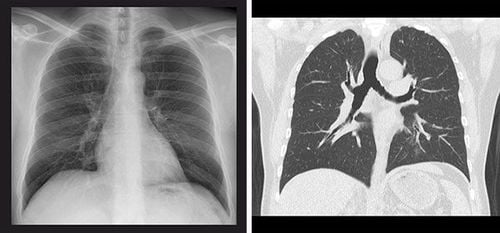

【楠本】日本では肺がん検診に胸部X線(レントゲン)と喀痰細胞診を推奨していますが、胸部X線では早期の肺がんを見つけるのはなかなか難しいといわざるをえません。通常、胸部X線では正面、側面から1、2枚しか撮影しないため、臓器の重なりで見えない部分が生まれますし、小さな肺がんも検出しにくいのです。

【楠本】世界的にも、肺がん検診は低線量CTが主流になっていますね。断層画像なので臓器の重なりによって隠れる部分がなく、画像の精度が高い。そのため小さい肺がんを発見しやすいというのが、導入の理由でしょう。さらに、欧米では胸部CTによって肺がんを見つけることで、より長生きできるかという視点で研究が行われています。2011年ごろから低線量胸部CTの有効性を示す研究結果が発表されていますね。

【福田】日本国内でも、喫煙歴などのリスクにかかわらず市民約3万3000人を対象にCT検診群と胸部X線検診群に振り分けて観察した結果、CT検診群で肺がんの死亡率が51%減少したという結果が出ています。喫煙者の方は肺がんのリスクが高いことは知られていますが、非喫煙者にも肺がんは起こります。この調査結果は、そういった方の早期発見にも胸部CTが役立つことを示しています。